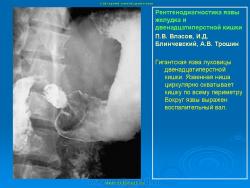

Пищеварительная система. Рентгенодиагностика язвы желудка и 12-ти перстной кишки. +

Рентгенодиагностика язвы желудка и 12-ти перстной кишки.

101.ya_.slayd45.jpg102.ya_.slayd46.jpg103.ya_.slayd16_1.jpg104.ya_.slayd17_1.jpg